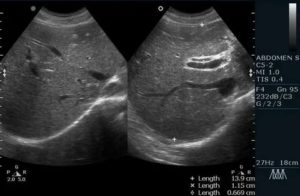

Каждый аппарат имеет специальное устройство, позволяющее доктору измерить все, что он видит на экране.

Измерить можно не только сам орган, но и его составляющие части: протоки, полости, отверстия и так далее.

Можно измерить ширину сосудов, которые идут к органу, отходят от него или находятся внутри органа. Можно измерить любое, обнаруженное образование: камень, опухоль, кисту и так далее.